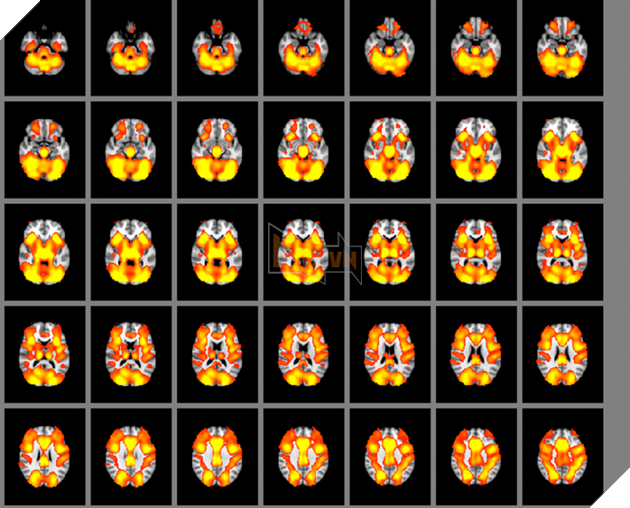

Một nghiên cứu mới đã chính thức tìm ra những bằng chứng chứng minh rằng, các game trí tuệ không hề có những khả năng đặc biệt trong việc rèn luyện não bộ, chúng cũng chỉ ngang hàng với những video game thông thường mà thôi. Nghiên cứu đã sử dụng các bài kiểm tra nhận thức và hình ảnh não bộ để đi đến kết luận trên.

Trong một nghiên cứu được công bố hôm thứ Hai trên tạp chí Neuroscience, 128 thanh niên đã được thử nghiệm về hiệu suất tinh thần sau khi chơi các game trí tuệ của Lumosity hoặc những video game thông thường sau 10 tuần. Các nhà nghiên cứu đã không thấy bất cứ bằng chứng nào chứng minh rằng những game “thể dục não” này giúp cải thiện trí nhớ, khả năng ra quyết đinh, khả năng tập trung lâu dài hoặc khả năng chuyển đổi giữa các bài kiểm tra tinh thần.

Bạn có thể đoán được một người đang cố bỏ thuốc sẽ thành công hay thất bại dựa vào dữ liệu hình ảnh não bộ của anh ta”, Lerman giải thích. “Mạng lưới điều hành của não” hay ECN, hoạt động thích cực hơn ở những người có thể bỏ thuốc. ECN là phần rất quan trọng đối với tự chủ bản thân, lên kế hoạch và thiết lập mục tiêu. Khi chúng ta tập trung vào một nhiệm vụ và hình thành bộ nhớ, ECN sẽ là bộ phận được hoạt động.

Một số nghiên cứu khác cũng cho rằng các bài kiểm tra nhận thức như các trò chơi trí tuệ có thể làm tăng hoạt động của ECN, nhưng rất ít nghiên cứu cho thấy có sự thay đổi tăng lên trong các hoạt động thường ngày khác.

Những tình nguyện viên được chia làm 3 nhóm, một nhóm chơi những game thông thường, một nhóm chơi game trí tuệ và một nhóm không chơi bất cứ game nào. Nhóm chơi game sẽ được chơi 5 lần/tuần, mỗi lần 30 phút. Họ cũng được kiểm tra định kỳ với nhiều bài kiểm tra về hiệu quả tinh thần khác nhau. Những người tham gia cũng được theo dõi để tránh các rủi ro không đáng có, trí nhớ, khả năng tập trung, và tính linh hoạt về nhận thức...

Khi so sánh giữa các nhóm, các nhà nghiên cứu không thấy bất kỳ bằng chứng nào về sự khác nhau giữa ba nhóm này trong các bài kiểm tra về nhận thức, những bài kiểm tra của họ được cải thiện đơn giản là do họ đã thực hiện lặp đi lặp lại các bài kiểm tra này mà thôi.